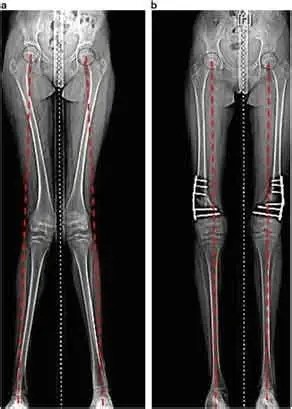

Bow legs, also known as genu varum, is a condition where the legs appear bowed outwards when standing. This condition can cause discomfort, pain, and even difficulty walking. In severe cases, surgery may be required to correct the alignment of the legs. In this article, we will discuss the causes, symptoms, and treatment options for bow legs, including the various surgical procedures available.

A doctor can diagnose bow legs by performing a physical examination and assessing the alignment of the legs. Imaging tests such as X-rays or MRI scans may also be used to confirm the diagnosis.

Knock Knees, also known as genu varum, is a condition where the legs appear bowed outwards when standing. This condition can cause discomfort, pain, and even difficulty walking. In severe cases, surgery may be required to correct the alignment of the legs. In this article, we will discuss the causes, symptoms, and treatment options for Knock Knees, including the various surgical procedures available.

A doctor can diagnose knock knees by performing a physical examination and assessing the alignment of the legs. Imaging tests such as X-rays or MRI scans may also be used to confirm the diagnosis.